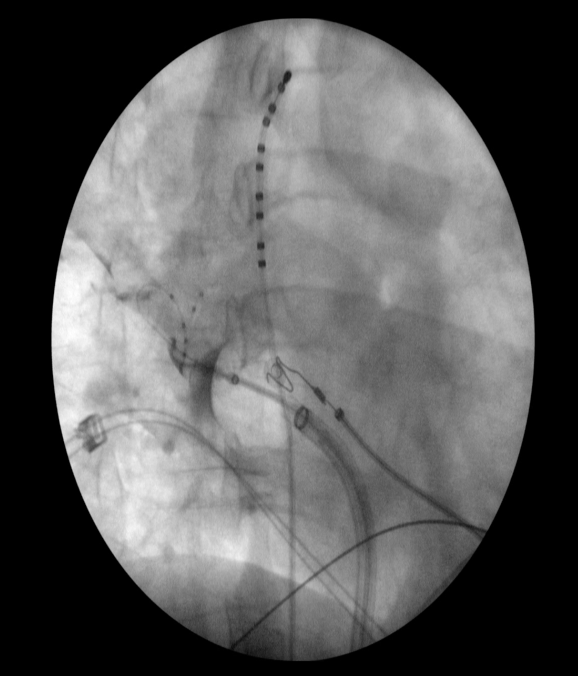

Left Bundle Branch Pacing. Hospital HIGA San Martin La Plata. Bs As #medtronic #ep #eppeeps